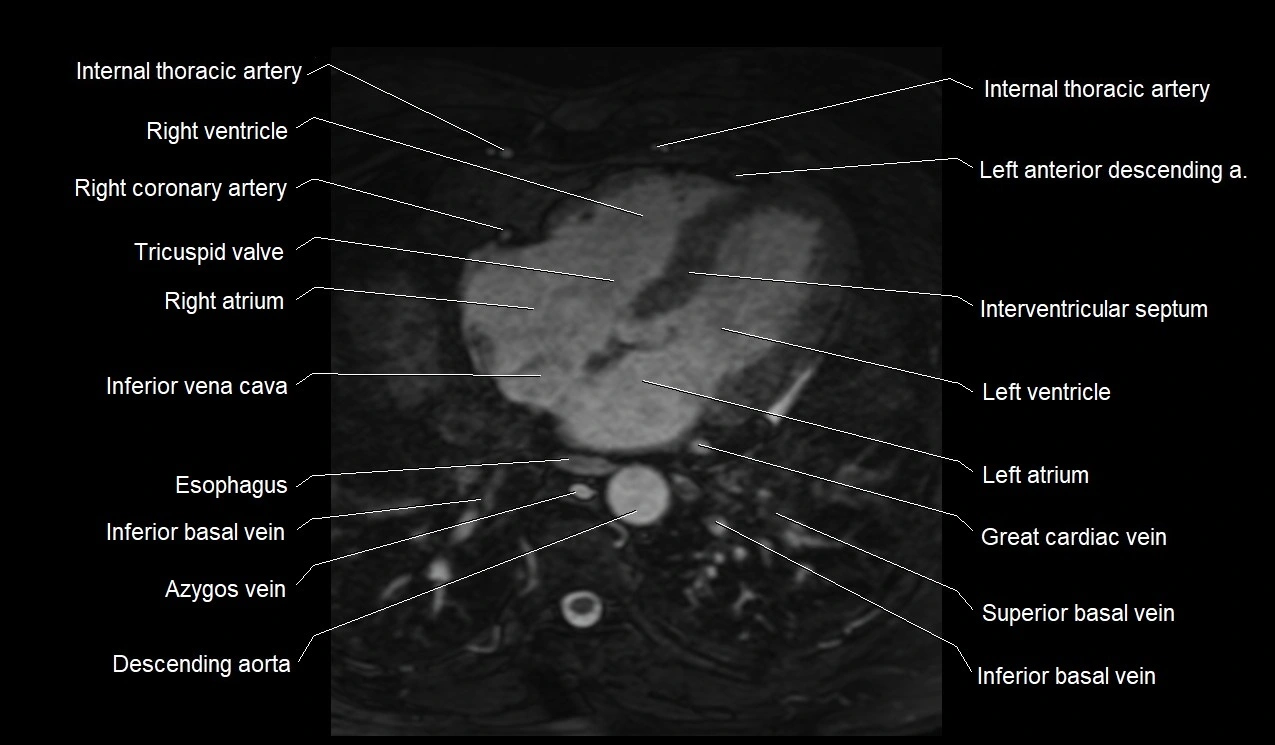

MRI image